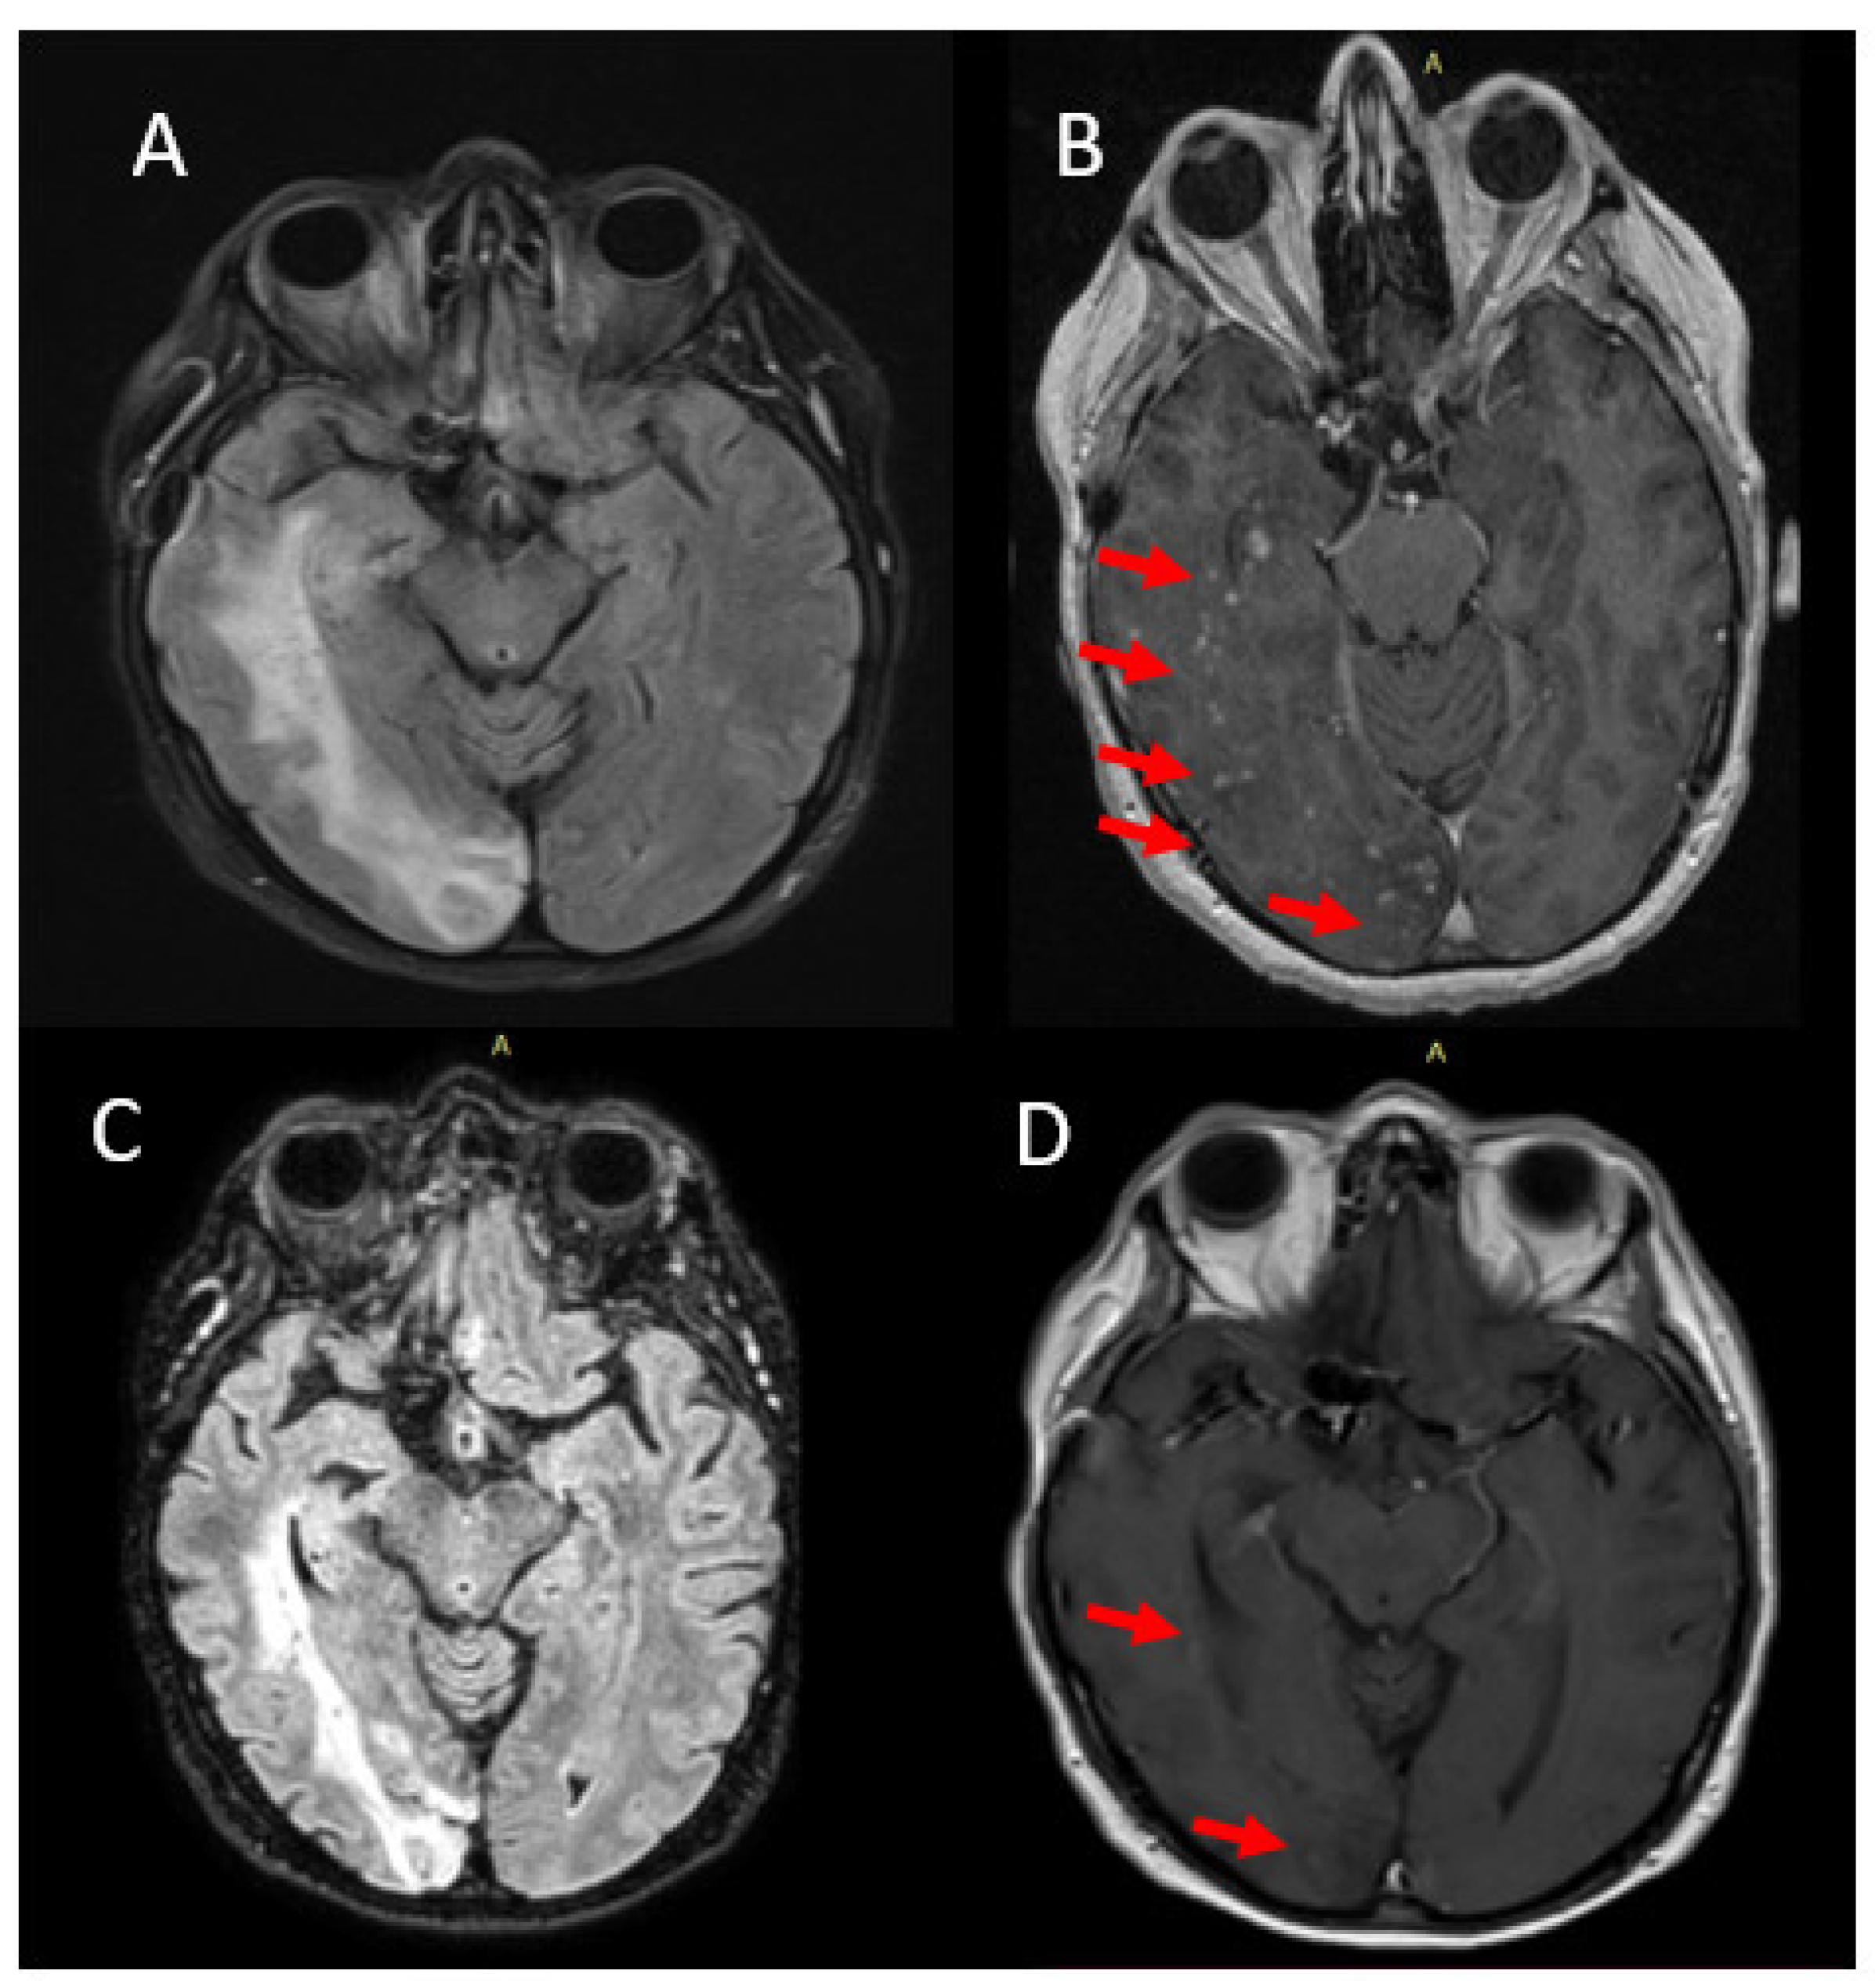

| Case 2 F/62 | Endovascular coiling/ right PCom | 6 months | left homonymous hemianopsia, left-sided hemiparesis, auditory hallucinations and seizures | Enhancing lesions, vasogenic edema, low SWI signals | No | Steroids **/improvement | 3 years |

| Case 3 F/49 | Flow diverter stent/ supraclinoid segment of left ICA | 6 months | gait disorders, right-sided hemiparesis, partial seizures of the right upper limb, mild cognitive impairment | Enhancing lesions, vasogenic edema, low SWI signals | Yes-chronic necrotizing granulomatous inflammation | Steroids **/improvement, recurrence after tapering | 1 year |